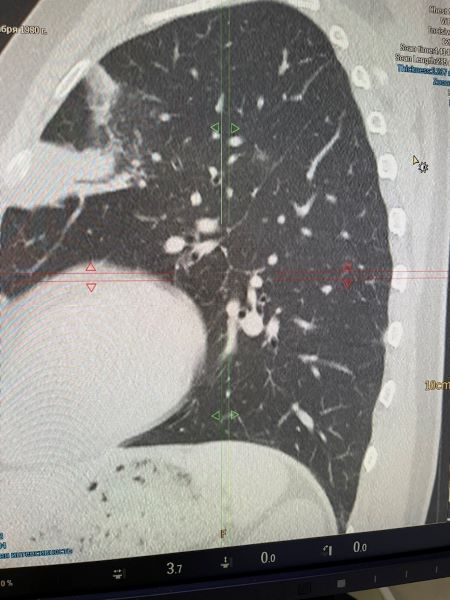

Левосторонняя полисегментарная пневмония

Мужчина, 43 года, считает себя больным около двух недель. Обратился с признаками респираторной вирусной инфекции по месту жительства.Пациент был обследован, сделано рентгенологическое обследование лёгких. По снимку - без патологии, назначено противовирусное лечение. Пациент выполнял все рекомендации, но сохранялся кашель с трудноотделяемой мокротой, желтоватого цвета и отмечал слабость во второй половине дня.

Самостоятельно обратился в клинику ВиТерра для обследования органов грудной клетки на МСКТ ( мультисрезовый Филипс ).